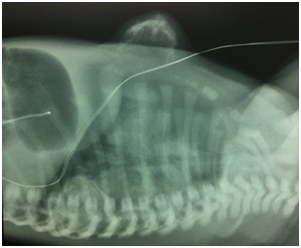

The neonate presented no signs of respiratory distress nor systemic failure. Plain radiograms shows the calcificated mass concerning to the 5th,6th, 7th ribs and the sternum with deterioration of the chest cavity Figures 2a&2b. Ultrasound of the area revealed a heterogeneous lesion, which casted significant acoustic shadow and was located symmetrically to the arches of the 6th, 7thand 8th left ribs. Multislice, low-dose CT scan was subsequently performed to clarify the origin, the extension and the configuration of the mass; 3D reconstructions were particularly helpful as they provided volumetric Figures suitable for preoperative planning Figures 3a&3b.

Figure 2a Plain radiogram of thorax. Is noted the large calcificated mass concerning to the 5th,6th, 7th ribs and the sternum.

Figure 2b Lateral plain film showing the protruding mass and the deterioration of thoracic cavity.